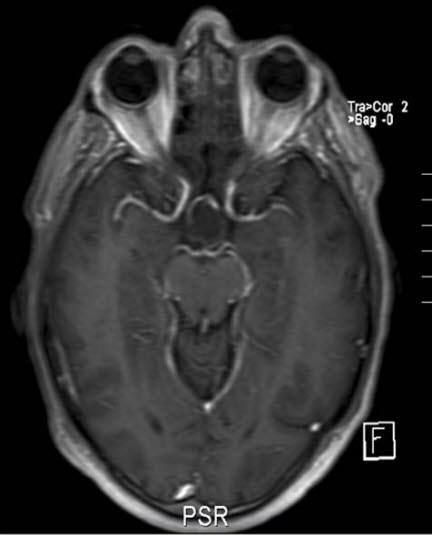

Kraniopharyngeom, aksialt snitt

Gjengitt med tillatelse av Radiologisk avdeling, Universitetssykehuset Nord-Norge